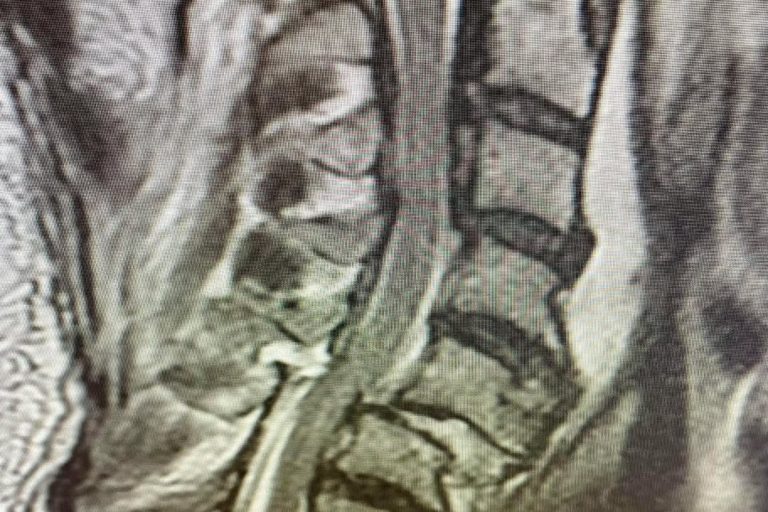

Meet Lin Sanders—a true inspiration of resilience and determination! Part 1 Lin underwent a complex two-level lumbar fusion at Texas Neuro-Spine Surgery. The procedure involved an anterior lumbar interbody fusion (ALIF) at L3-4 and L4-5, followed by laminectomies and pedicle screw instrumentation at the same levels. These surgeries were performed to help address her back…